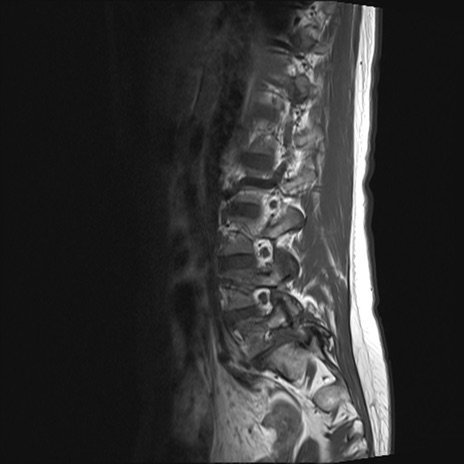

【整形】TIPS症例4 腰椎MRI T1WI(矢状断像)

腰椎MRI

T2WI(矢状断像)